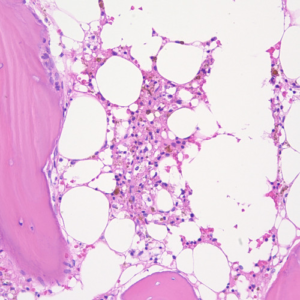

Come si vede nella foto, nel bambino piccolo il midollo osseo è ubiquitario, mentre nell’adulto si riduce al tronco, al bacino, alla testa, scomparendo dagli arti più stimolati meccanicamente.

Da notare che la scomparsa del midollo osseo rende l’osso nel suo insieme incapace ad adattarsi ai cambiamenti del carico. L’aumento delle fratture del collo del femore nell’anziano deriva dalla scomparsa con la menopausa del midollo osseo dal collo stesso.

Quando tali cellule non riescono a proliferare perché gli manca un elemento essenziale come il ferro, essi utilizzano tutti i nutrimenti disponibili e soprattutto il glucosio per trasformarsi in adipociti.

Questo conferma il dato che gli adipociti non sono diversi strutturalmente dalle cellule che proliferano ma differiscono da queste in funzione della disponibilità di nutrienti ambientali nella nicchia in cui si trovano.